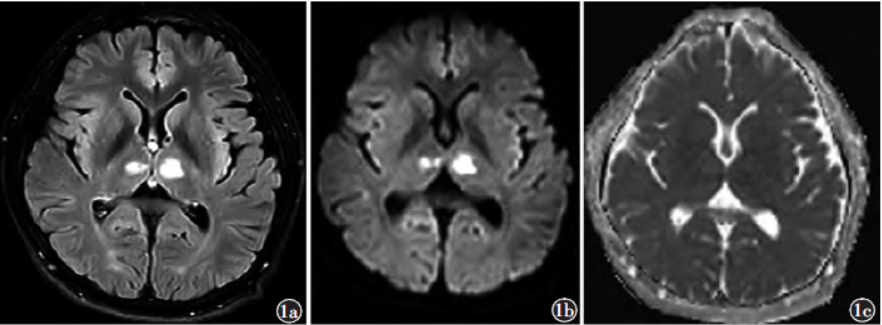

影像学检查:头颅MRI及MRA(图1~3)示双侧丘脑及左侧小脑半球多发斑片样T1WI低信号影、T2WI高信号影,T2WIFLAIR呈高信号,DWI信号随b值升高并增高,ADC呈低信号。DSA(图4)示Percheron动脉起源于左侧大脑后动脉P1段近段,右侧丘脑穿通动脉分支显影纤细,左侧丘脑穿通动脉分支血流缓慢。

图1MR扫描a)T2FLAIR轴位示双侧丘脑斑片状高信号;b)DWI示双侧丘脑病灶高信号;c)ADC示双侧丘脑病灶低信号